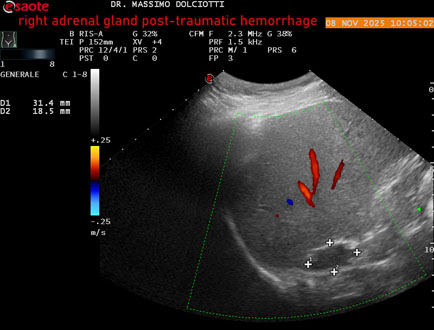

Data inserimento: 10/11/2025

Ecografia del: 08/11/2025

Strumento: Esaote MyLab Eight

Sonda: Convex Multifrequenza 1-8 MHz

Età Paziente: M 49 anni

Motivazione dell'esame: follow up per emorragia al surrene destro post-traumatica (incidente stradale).

Commento all'esame: le immagini ed il video documentano in sede surrenalica destra, formazione ipo-anecogena, a margini definiti, ovalare, delle dimensioni di 38,6 x 19,7 mm, da ricondurre ad emorragia post-traumatica.

Conclusioni: emorragia post-traumatica al surrene destro (post-traumatic hemorrhage to the right adrenal gland).

Presentazione: Dr. Massimo Dolciotti - Ancona

Elaborazione digitale: Andrea Dini - Ancona